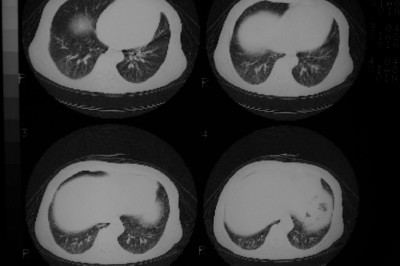

以下是引用天南地北在2007-4-10 1:49:00的发言:[br]考虑右下叶周围型肺癌伴肋骨转移。

以下是引用jone-baby在2007-4-10 8:45:00的发言:[br][br] [br] 患者[br]有发热史,x线片考虑肺脓肿.肺脓肿可以导致肋骨破坏吗?[br]脓肿可以排除吗? [br] [br] [br]

以下是引用林建春在2007-4-10 7:35:00的发言:[br]周围型肺癌侵犯肋骨

以下是引用liuyue在2007-4-10 7:56:00的发言:[br]周围型肺癌侵犯肋骨,左肺转移。

以下是引用zhangzhongshou在2007-4-10 10:24:00的发言:[br]右肺下叶背段厚壁空洞,伴胸膜改变、肋骨破坏,其内可见死骨、周围骨质硬化,左肺可见小结节影,[br]单纯影像学更支持结核。建议进一步检查。